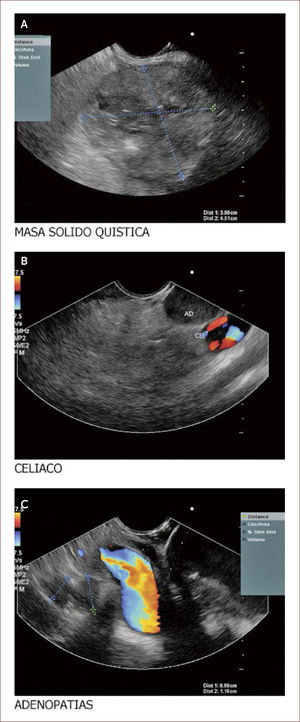

Compromete vía biliar y tiene múltiples adenopatías. Se ve también involucrado el Wirsung. La patología reportó un adenocarcinoma mal difereciado del páncreas. En la foto A se ve la masa y en está igual que en la de la derecha se ve que contacta e invade la porta. En la B se ve un nódulo grande entre la porta y la lesión de la cabeza. Con estos hallazgos más la clínica del paciente el grupo de cirugía decidió manejo paliativo. Colocamos en vía biliar un stent autoexpandible no recubierto. El paciente está aún en seguimiento. (imagen de Unión de Cirujanos SAS – Lázaro Arango (Autor), se publica con permiso).

Paciente de 60 años con masa que emerge de la cabeza del páncreas y llega al borde inferior del hígado. En la imagen A se ve la masa. En la B la aorta a nivel del plexo celíaco y una gran adenopatía a este nivel. En la C se ven los vasos portales y adenopatías varias a este nivel. Esta paciente se llevó a punción y se reportó un sarcoma mal diferenciado. La paciente no fue llevada a ningún procedimiento quirúrgico. (Imagen de Unión de Cirujanos SAS – Lázaro Arango (Autor), se publica con permiso).